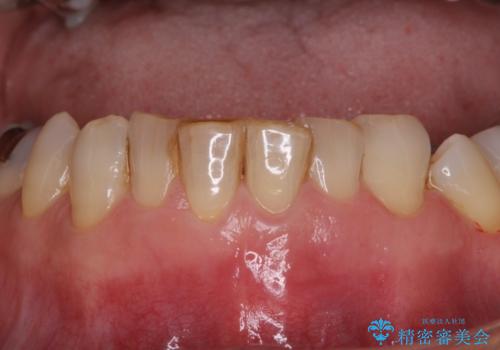

- 下顎前歯が痛んで近医を受診したところ、下顎前歯2本を抜歯してインプラント治療が必要と診断されたとのことで来院された患者様です。

診査の結果、下顎左側中切歯の神経が失活していることが痛みの原因であり、根管治療を行う必要があると診断されました。

根管治療を行った後にオールセラミッククラウンにて補綴することとしました。

隣在歯にも根尖部の炎症が及んでいるように見えましたが、術前診査では神経が失活している様子がなかったため、まずは原因歯から処置を行うこととしました。

初回の根管治療後には痛みが速やかに改善し、6か月後のレントゲン写真では根尖の病変が消失していることが確認できました。